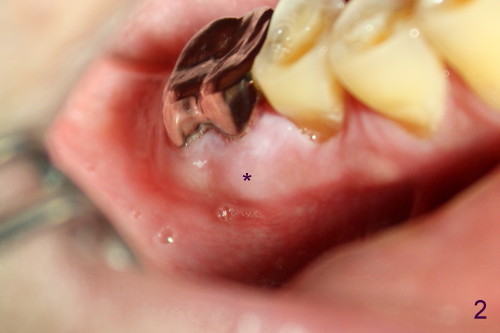

如以前介绍()右下第一磨牙近中根尖阴影根管治疗后逐渐增大(图一*),最后病人同意做根切,术前颊侧观显示近中根尖处肿胀(图二*),前庭沟挺深的,暴露可能不错(金杭晴理论),但如何做切口呢?根尖附近半月形切口(图三),还是牙龈沟切口附加斜形切口(图四)?结果

Probably due to our similar background (oral surgery), I chose surgical mode. I particularly like your idea: 根切的关键在于前庭沟浅还是深,深好做,因为暴露好。In fact the vestibule is deep in this case as will be shown soon in my web. What incision should I make, gingival sulcus or apical semilunar, for the best exposure? Xin Fri, 3 May 2013 18:22